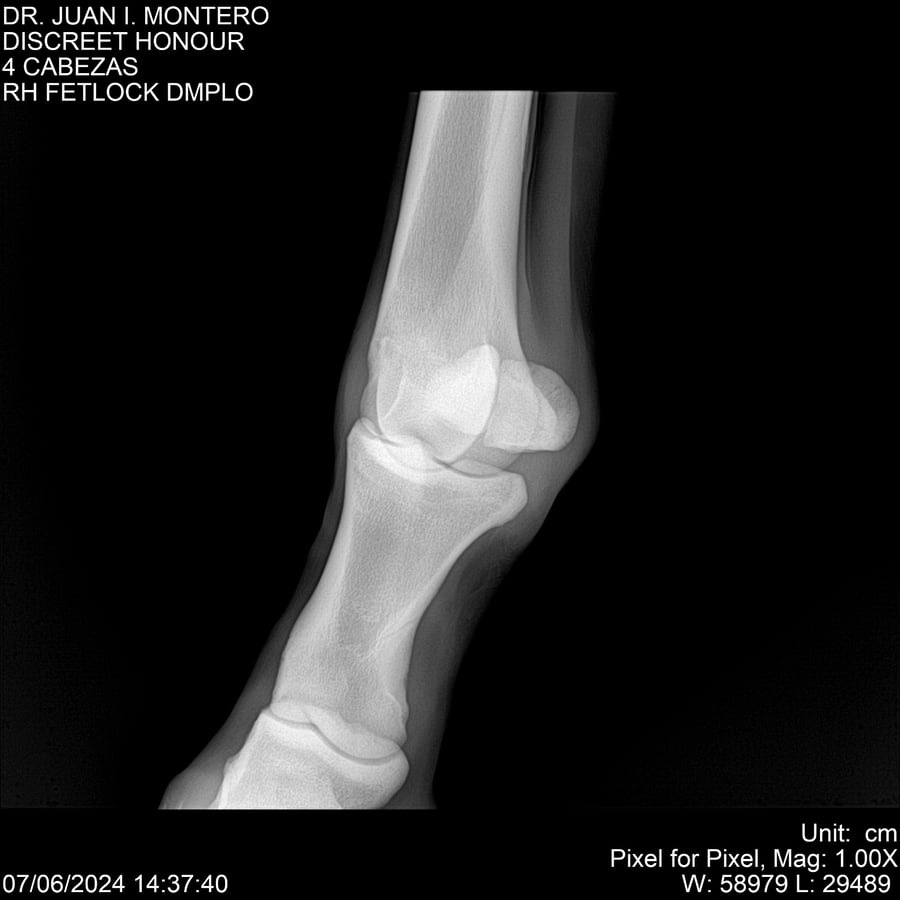

LOTE 6, DISCREET HONOUR 🔥 🔥 🔥 Lote Anterior Volver al remate Lote Siguiente Ficha Contacto Montevideo - Ficha del Lote Identificador: #281093 Categoría: Yeguarizos Montevideo - 82 Visualizaciones ClicData Contacto Empresa: Abelenda N. R., Walter Hugo Nombre*: Teléfono* : E-mail* : Mensaje Enviar Registrese gratis Este contenido Exclusivo está disponible sólo para usuarios registrados Ingresar